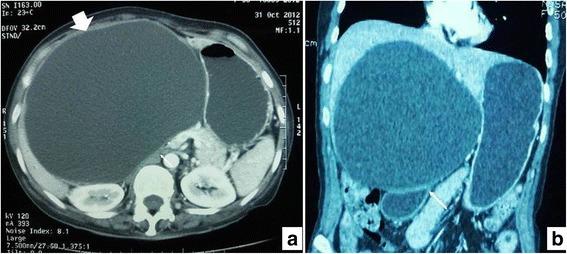

All of these cases were resected with the clinical and/or radiological impression of simple liver cysts and/or hydatid cysts. Out of the six patients, five were female and one was male. Ages of the patients ranged from 28 to 60 years (mean 45 years). The patients presented with nonspecific symptoms. Internal septations were seen on preoperative imaging (when available). On gross examination, all tumors were cystic; their sizes varied from 5.5 to 14 cm, mean size was 9.0 cm. On histopathologic examination, cystic spaces were lined by cuboidal to columnar mucin-secreting epithelium with underlying ovarian-type stroma. In one case, ovarian-type stroma was not seen. Recurrence was seen in three cases at 1 to 5 years of follow up.